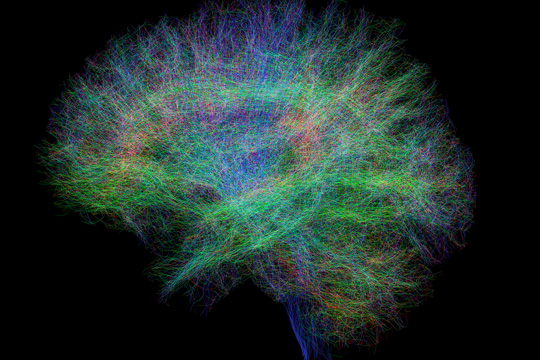

脳のやわらかさを

希望に変える

脳がやわらかく変化する可塑性を研究し、医療に応用するためのテクノロジーの開発やアプリケーションのデザインを行っています。